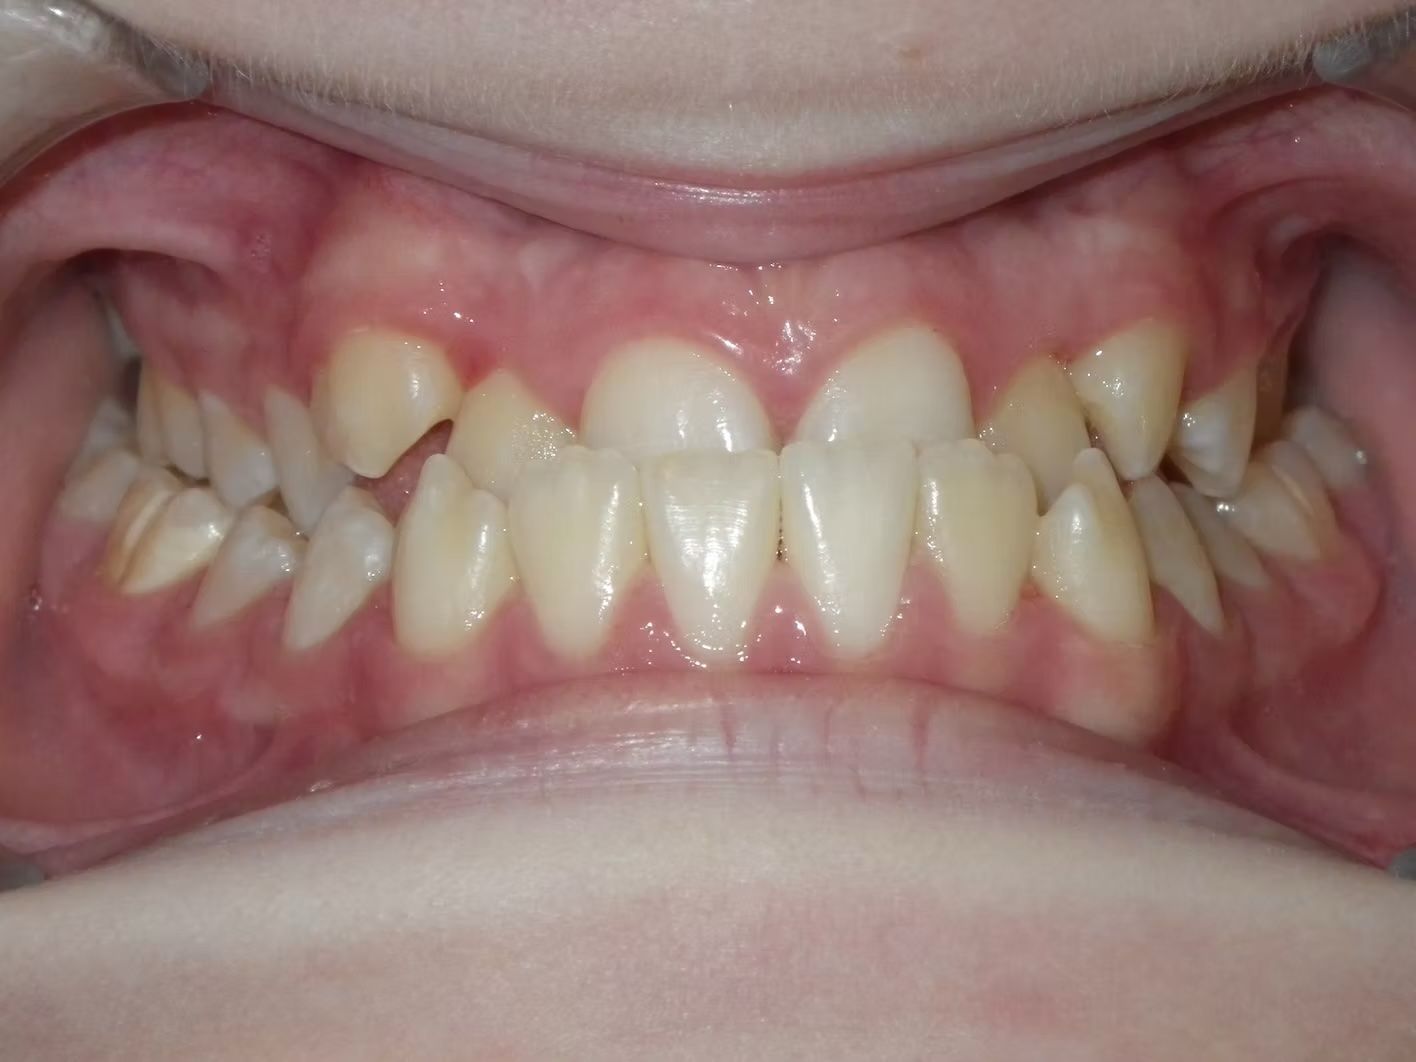

IAN

Ian came to the office because his lower teeth were crowded and he had an anterior cross bite. With traditional braces we resolved the crowding and aligned the teeth without causing flaring of the incisors and giving him a handsome smile. The treatment lasted 18 months and the final photos are at a 2 year follow up when we made him a new clear retainer.